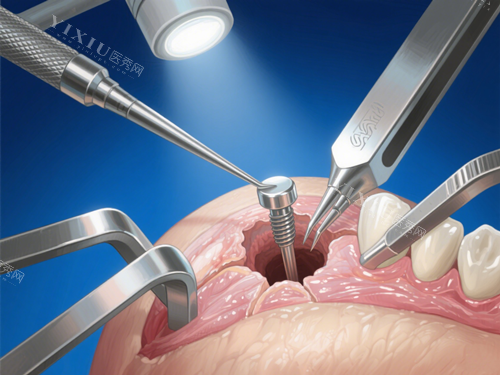

种植修复类

进口种植牙(含种植体+基台+冠):5200元起

瑞士ITI种植系统:12800元起

韩国奥齿泰种植系统:6800元起

全口半固定种植修复:38000元起

即刻种植牙(单颗):8800元起